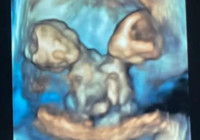

Ultrasonda gördüğü anda dünyası başına yıkıldı! Genç annenin zor seçimi...

Genç annenin zor seçimi... ABD'de yaşayan genç bir anne adayı, ultrasonda yapışık ikiz taşıdığını görünce hayatının en zor kararına itildi. Çift, doktorların tüm uyarılarına rağmen ikizleri dünyaya getirmeyi tercih etti ancak bebeklerin ömrü uzun olmadı...